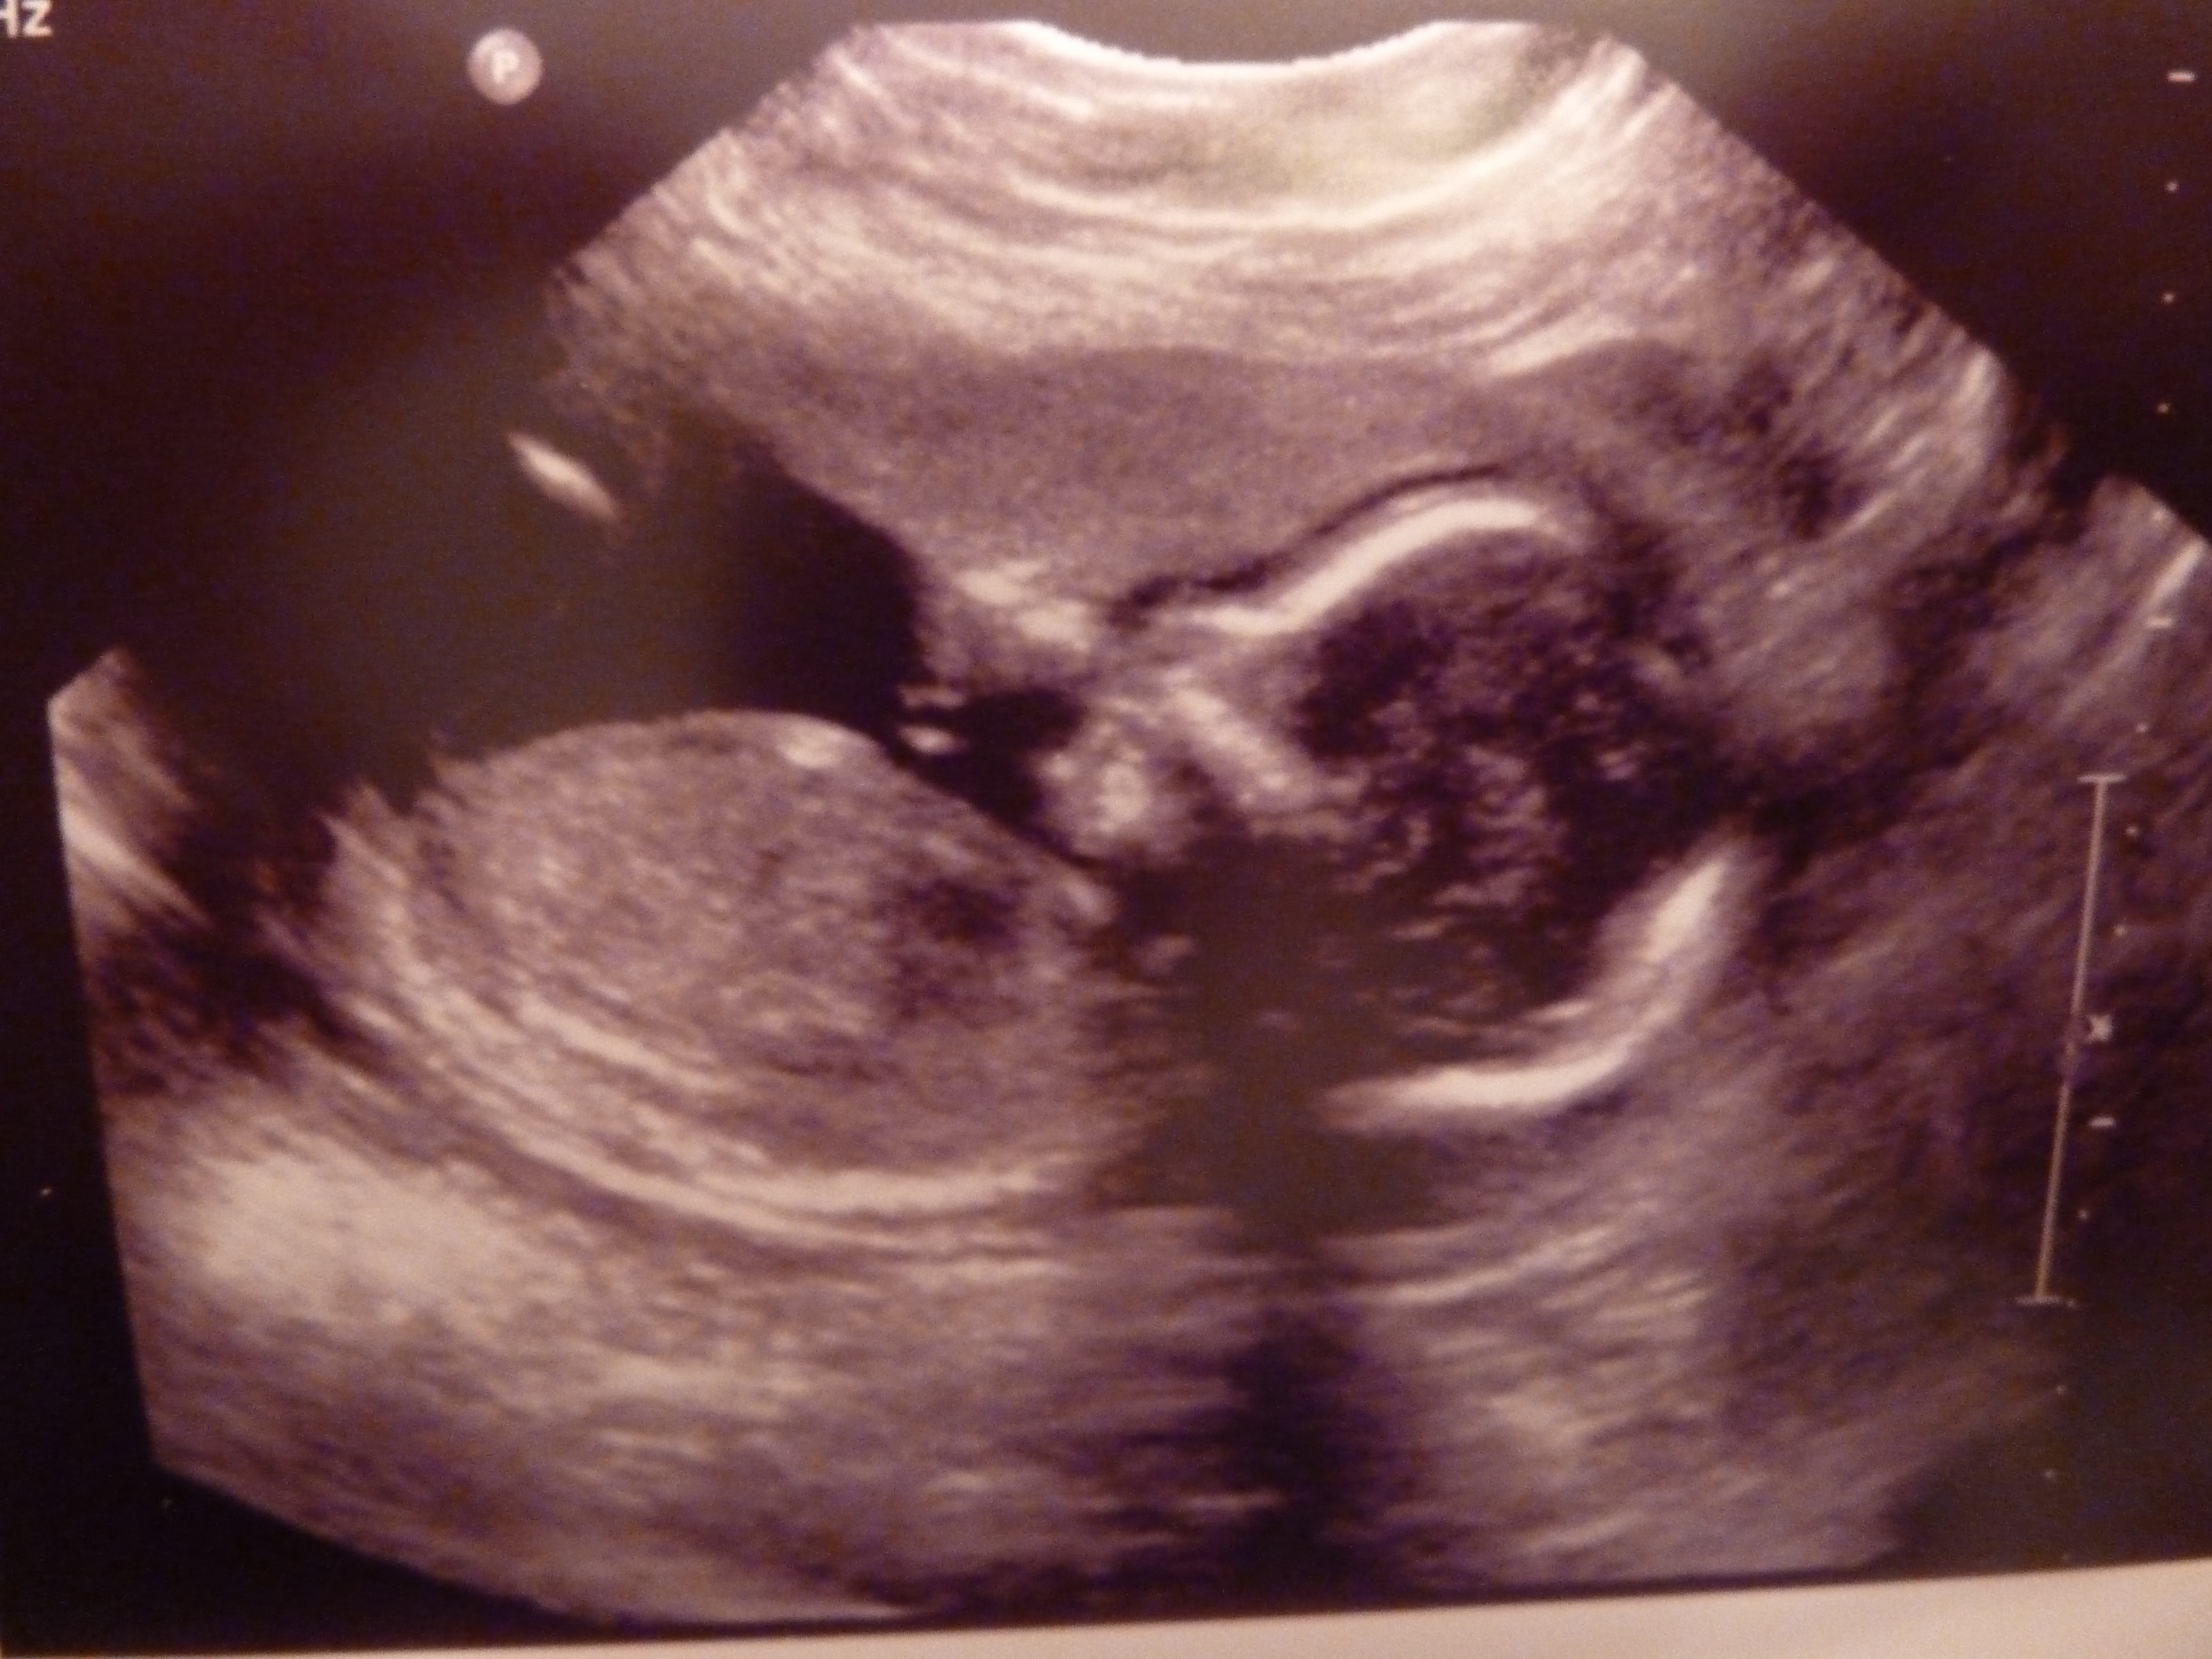

So, I had my big 20-week sonogram this afternoon and…

P1160894

The best news of all is that baby #3 looks perfectly healthy. (And judging from all the jumps I’m feeling, also quite happy!)

P1160893

Just like my first two, this one didn’t cooperate too well with the test. It took three goes for the technician to get all the information she needed.

P1160892

However… baby wasn’t at all shy about revealing gender.